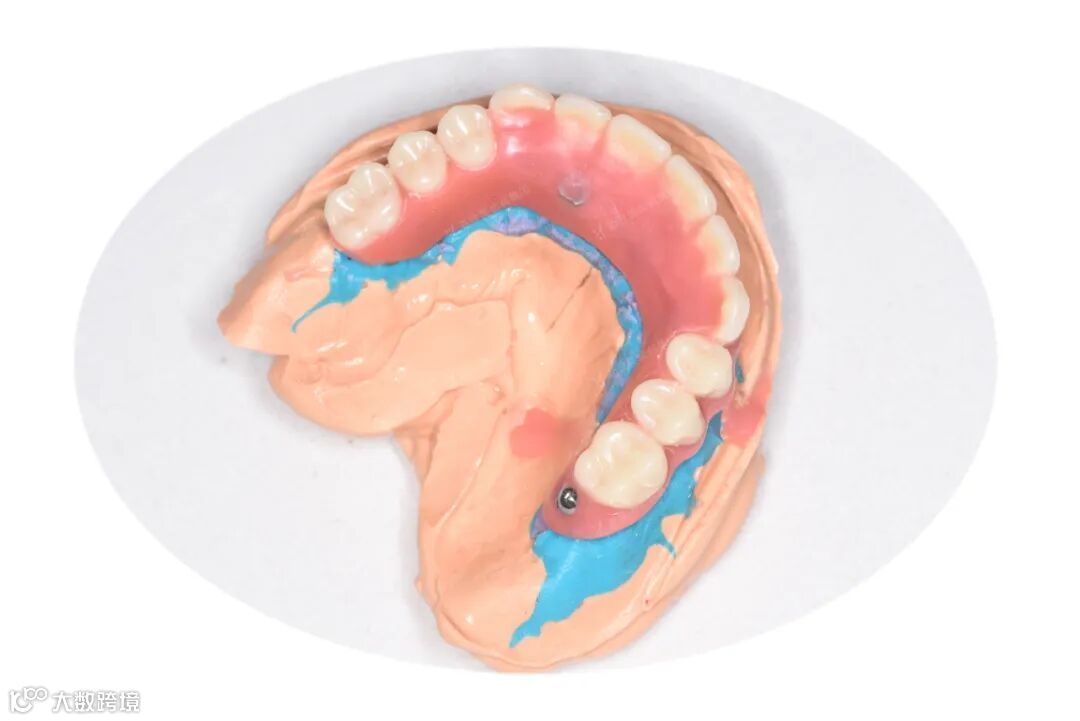

取模过程

即刻负重修复体制作过程